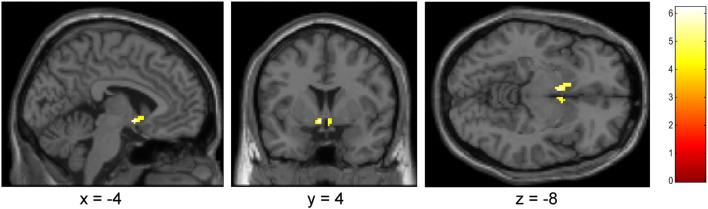

An a priori defined region of interest (ROI) analysis of fMRI data from 15 participants revealed that nalmefene reduced alcohol cue-reactivity in the ventral, but not the dorsal striatum. Additionally, the subjective craving was significantly reduced after the cue-reactivity task under nalmefene compared to placebo.

15 名参与者的 fMRI 数据的预先定义的感兴趣区域(ROI)分析显示,纳美芬降低了腹侧纹状体而非背侧纹状体的酒精线索反应性。此外,与安慰剂相比,在纳美芬下进行线索反应性任务后,主观渴求明显降低。